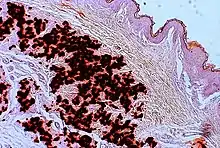

The diagnostic criteria for PXE are the typical skin biopsy appearance and the presence of angioid streaks in the retina. Criteria were established by consensus of clinicians and researchers at the 2010 biennial research meeting of the PXE Research Consortium.[29] and confirmed at the 2014 meeting[30] These consensus criteria state that definitive PXE is characterized by two pathogenic mutations in the ABCC6 or ocular findings – angioid streaks > 1 DD or peau d’orange in an individual <20 years of age together with skin findings:

- Diagnostic histopathological changes in lesional skin: Calcified elastic fibers in the mid and lower dermis, confirmed by positive calcium stain

| Pseudoxanthoma elasticum | LM: Mid-dermal calcification and fragmentation of elastic fibers EM: Mineralization in elastic fiber core |